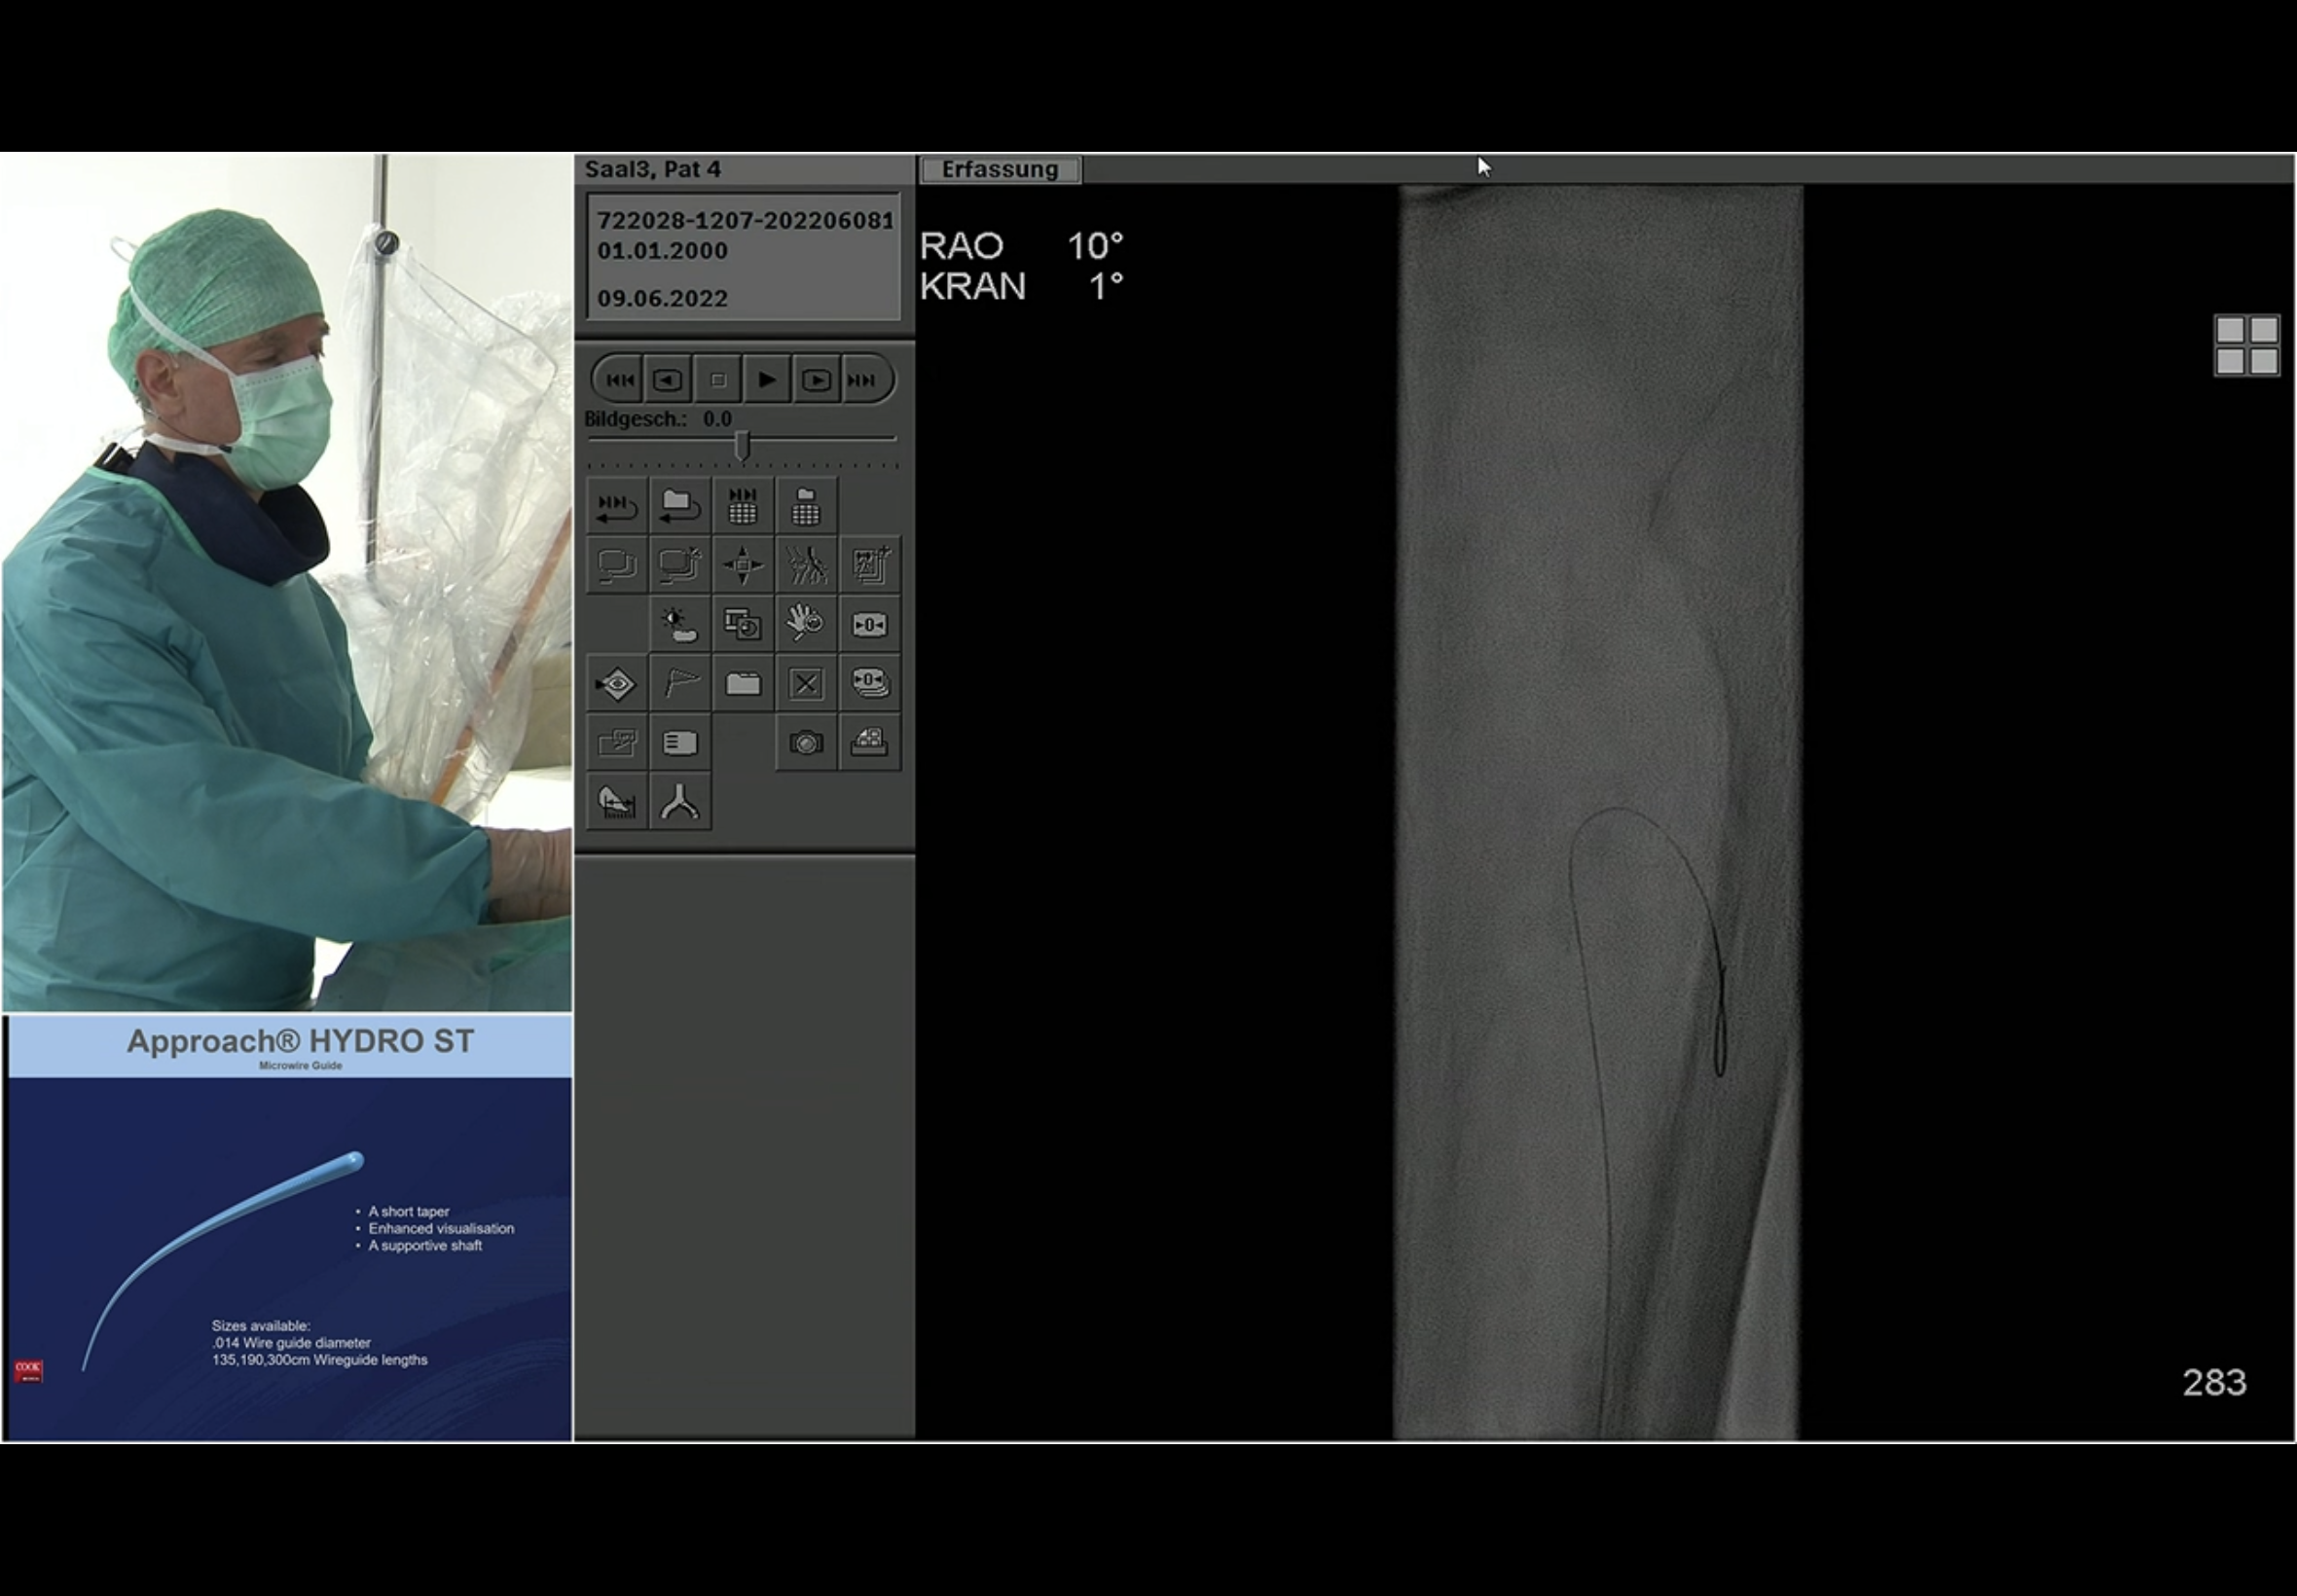

Fluoro roadmap guided puncture of the PeA. The seen vessel here is the PTA. Andrej emphasises that needle path should be parallel to the target vessel. He states that the approach to the vessel is “anterior”. The C-arm looks to be in an ipsi oblique - this is the left leg and the angle is LAO 29 on the image just before the magnified view with the needle; that is the impression I had at the time too. He then reverts to a contralat oblique RAO view to corroborate needle position and entry and then continues to work in that view.

He does the next DSA to confirm for certain that he is indeed in the PeA and not the PeV; the PeA is seen outlined lightly but certainly overlying the wire coming up from below.